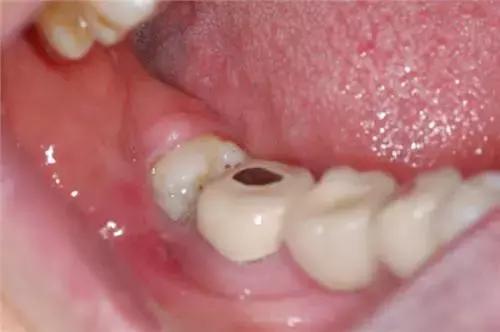

1、 由于萌出不全,后侧的牙龈覆盖,其部分牙冠形成冠周袋积存食物和细菌,可以造成局部软组织经常发炎,疼痛难忍,甚至导致张口受限而进食困难。

4、 会影响其他牙齿龋坏:阻生智齿能使第二磨牙龋坏。向前倾斜的智齿,其牙冠顶在前牙的颈部,这两颗牙之间形成一个滞留区,由于食物残渣的滞留,得不到正常清洁,细菌繁殖产酸,腐蚀牙齿,造成第二磨牙牙颈容易发生龋齿,往往就诊时已不能保留,需要拔除。